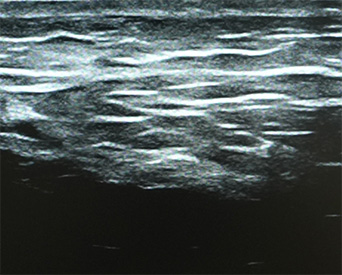

기존 울쎄라 초음파는 8mm 깊이까지만 확인 가능해

지방층이나 뼈 깊이 등 피부 내부 전체 구조를 보기 어렵습니다.

이를 보완하기 위해 더퍼스트피부과는 4cm 깊이까지 확인 가능한

최신형 진단 초음파 장비를 도입하여 피부 진피-지방-근육-뼈 깊이까지

정밀하게 파악하여 에너지와 샷수를 조절하는 시술 플랜을 세웁니다.

피부층의 깊이, 밀도나 노화정도를 파악하고 이전의 수술력이나 특이사항도

분석 가능하여 얼굴에 금속핀이 있는 경우에도 시술이 가능합니다.

울쎄라 초음파

DEEP SONO™ 초음파